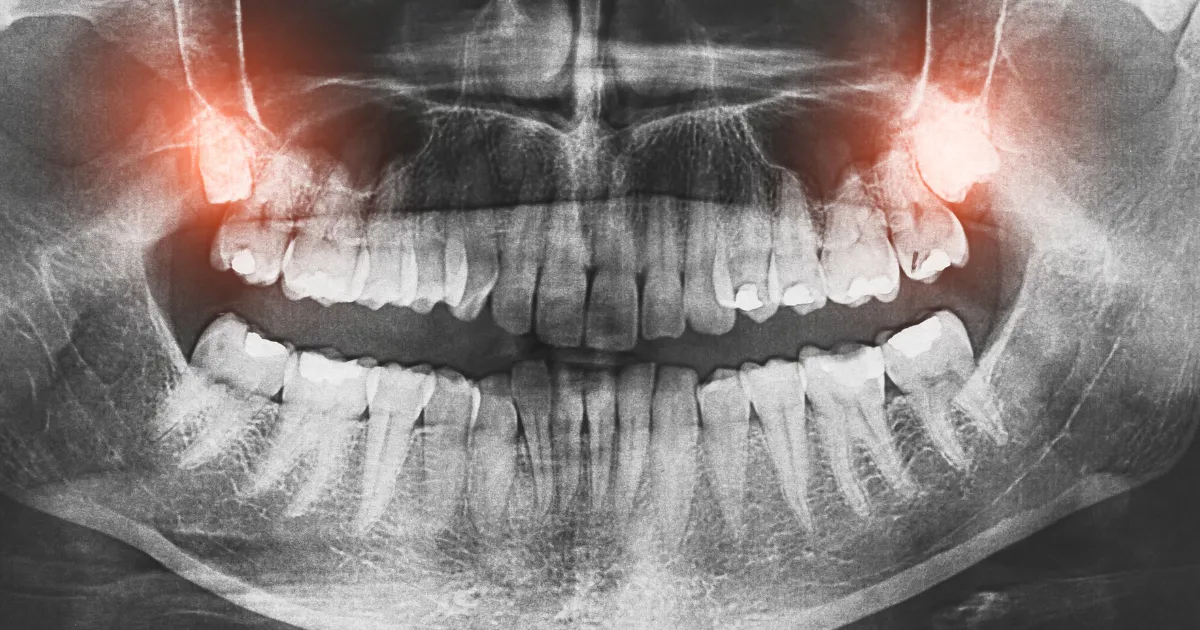

親知らずの抜歯は通常は外来(一般病院のチェアーサイド)で行われますが、状況によっては大学病院での入院が必要になることがあります。

特に難抜歯や全身の健康状態によっては歯科医師より入院の提案がされることもあります。

親知らずの治療で入院が必要なケース

親知らずの抜歯がすべて入院を必要とするわけではありませんが、以下のケースでは入院が推奨されることがあります。

- 症状が重たい方

- 複数の親知らずを同時に抜く方

- 全身の病気を持っている方

- 精神的な問題を抱えている方

症状が重たい方

親知らずが非常に深く埋まっている場合や、周囲の歯や骨に影響を与えている場合には、入院が必要になることがあります。

複数の親知らずを同時に抜く方

一度に複数の親知らずを抜く場合、入院を選択することがあります。

これにより全身麻酔での手術が可能となり、短期間での治療を完了させることができます。